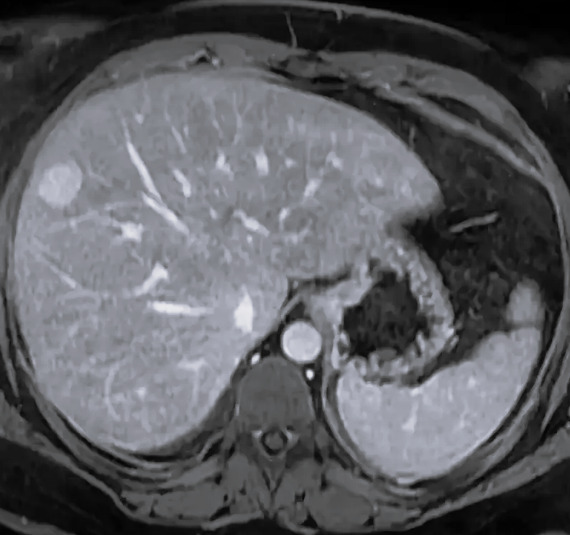

Мрт рака печени

Мрт рака печени 112 фото